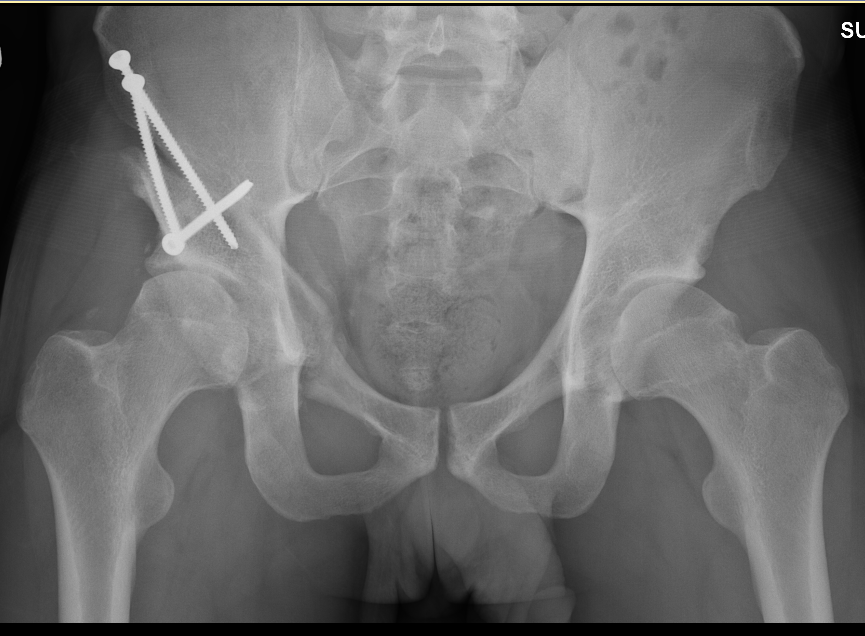

From exythyinv.blob.core.windows.net

Can An X Ray Tell If You Need A Hip Replacement at Jean Stevenson blog Hip Replacement No Cartilage Daniel wiznia, md, an orthopaedic surgeon with yale school of medicine, is practicing a surgical technique designed to render 10% of hip replacements. Within one year, the defect is. Hip replacement surgery is a common procedure that is necessary when the hip joint is worn or damaged. Smaller lesions can be treated with transplants of the patient’s own cartilage. By. Hip Replacement No Cartilage.